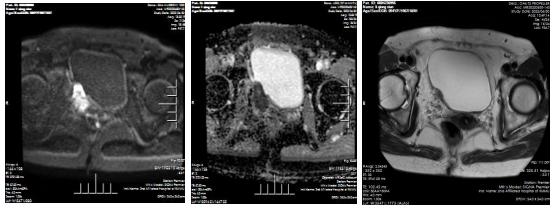

入院后,张劲松主任医师对该患者进行了详细病史询问和术前检查,重点了解了患者13年前肾移植情况、术后免疫抑制剂使用药物类别和剂量及既往手术史。随后,完善盆腔多参数磁共振检查和取活检结果,术前诊断为膀胱高级别浸润性尿路上皮癌。术前查血常规、凝血、肝功能、肾功能、胸部CT、心电图、心超等均未见明显异常。